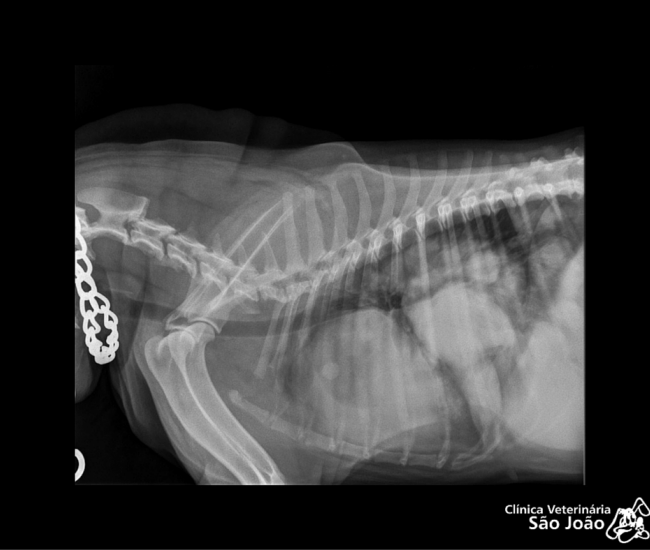

- Diferentemente do raio-x analógico, este raio-x oferece altíssima definição e todas as vantagens da tecnologia digital. É possível aproximar a imagem, trabalhar o contraste, exposição.O software permite ainda avaliações da medida cardíaca do animal e graus de displasia coxofemoral, por exemplo – explica o Dr. Nardeli Lucena.

- melhor qualidade da imagem;

- melhor detalhamento técnico;

- diagnósticos mais precisos;